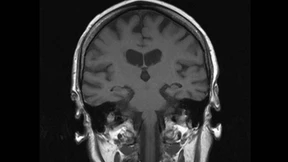

Demenz wird in einer alternden Gesellschaft zur Volkskrankheit. Pharmakonzerne sehen darin ein Geschäftsfeld, Angehörige eine psychische Last.